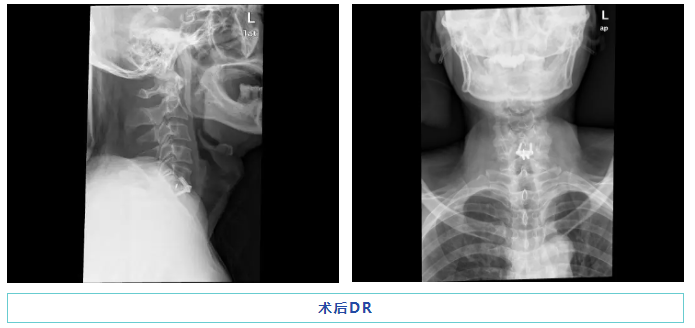

在显微镜的辅助下,术中,赵斌修和吴茂聪博士顺利完成了颈前路椎间盘切除和零切迹融合器融合手术,术中出血量仅约5ml,切口不到4cm,手术在2小时内顺利完成。而微小的手术创口也为伍先生的术后恢复打下了良好的基础,不仅降低了并发症的风险、也使恢复时间得到缩短。术后患者情况良好,左上肢麻木疼痛症状明显缓解,回家后的康复进展也较顺利。